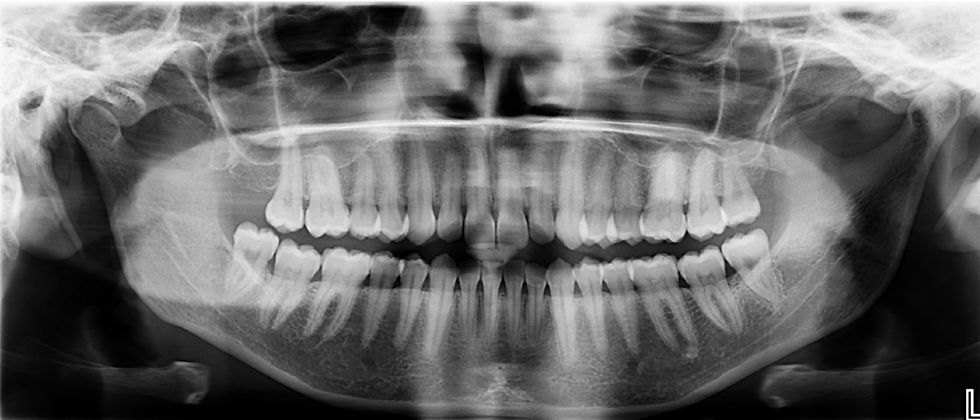

Radiographie panoramique :

Ce cliché radiographique d’établir la formule dentaire et de localiser les germes dentaires, de visualiser le niveau de l’os, de mettre en évidence un kyste ou une dent incluse, de suspecter une ou plusieurs caries/fractures, de contrôler l’axe des racines, de localiser le nerf dentaire, de visualiser la présence ou non de résorptions radiculaires etc…

Lorsque le traitement orthodontique est initié, votre orthodontiste au Cannet réalisera environ tous les 6 mois des radiographies panoramiques afin d’évaluer le niveau osseux ainsi que pour s’assurer de l’absence de résorptions radiculaires.